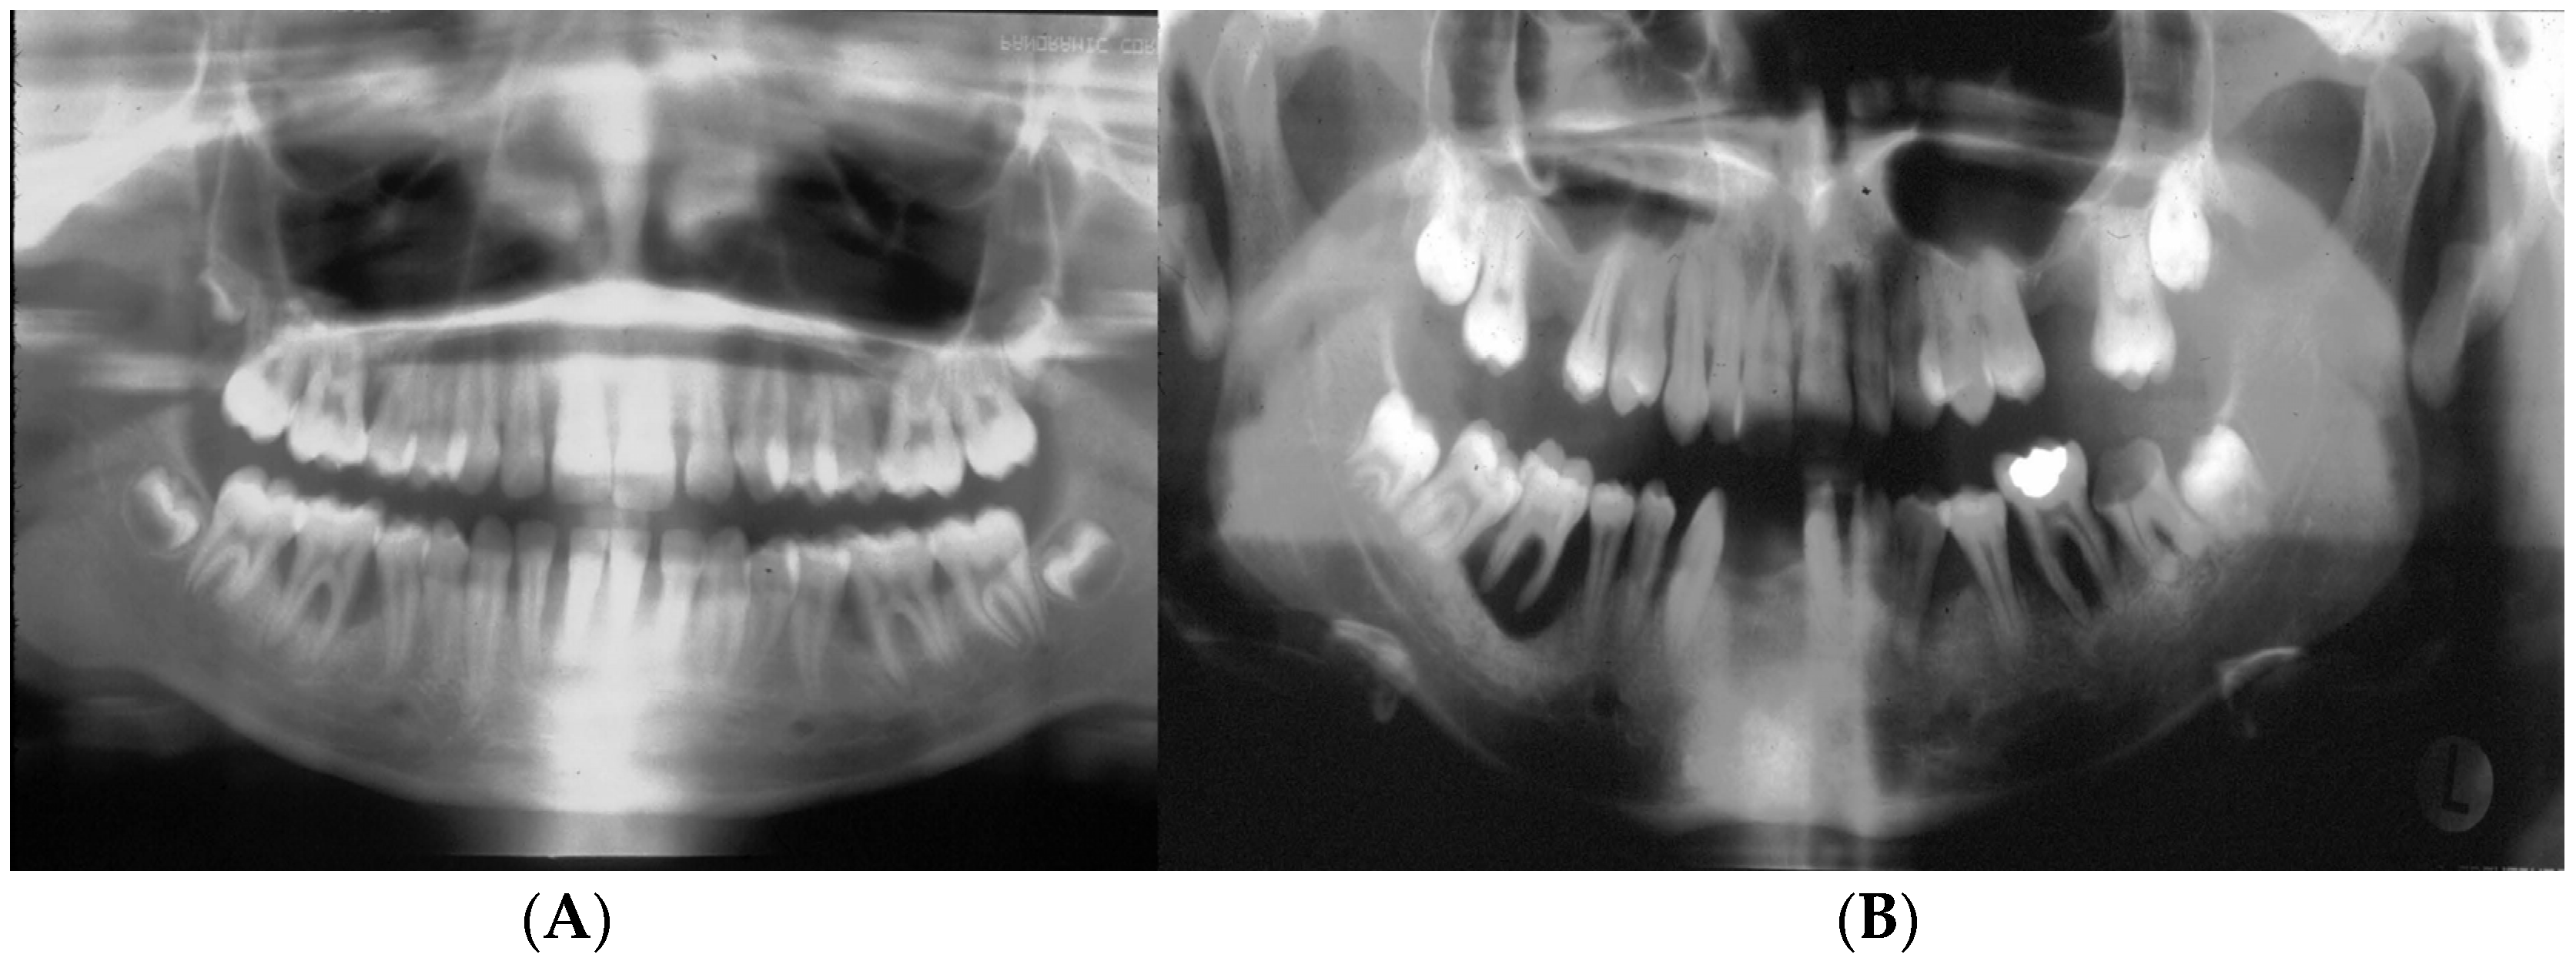

This case is presented to illustrate the distinctive nature of aggressive periodontal bone loss in a 20-year-old patient who reported to our clinic (RSDM) with extensive periodontal disease. After obtaining consent (IRB:PRO#012008035; year = 2009), we collected subgingival plaque, saliva, and buccal cells for analysis. The subgingival sample taken from various healthy and diseased sites had the “b” serotype of Aa with the JP2 promoter region. The patient had only one strain of Aa in his subgingival microbiome isolated from both healthy and diseased sites, with substantially more Aa isolated from diseased sites. We tested the Aa isolates for antibiotic sensitivity and for the presence of the hbpA-1, hpbA-2, and tbp-A pseudogenes using primers reported by Haubek et al. [153]. Saliva was assessed for salivary anti-S. mutans activity and buccal cells were used for the detection of the lactoferrin (LF) single nucleotide polymorphism associated with anti-S. mutans activity [154]. Our primary goal was to use our laboratory data to provide information about Aa antibiotic sensitivity, which could act as a supplement to treatment aimed at resolving this progressive disease in this young patient. The focus on Aa was pragmatic because our previous data had suggested that Aa was necessary but subsequently proved to be insufficient on its own to cause disease [29]; conversely, assessment of the complete consortia was impractical at that time. However, several of our other laboratory assessments proved useful.

While we recovered Aa from the diseased site, we cannot attribute disease to the presence of Aa. Microbial causation can only be implied if the bacterium preceded disease at the site of disease initiation [41]. Therefore, in this case, linking Aa to disease initiation and development can only be seen as speculative. Second, based on the complex patient history, it is reasonable to conclude that confounding social, psychological, and ecological modifiers could have contributed to a diminished host response, factors that could clearly be implicated in disease progression [42]. Based on antibiotic sensitivity testing, we ruled out the use of penicillin derivatives due to Aa insensitivity, which was a clinically useful finding. Furthermore, the age of the patient, the tooth loss attributed to periodontal disease, and the extent of bone loss indicated an aggressive nature of localized disease in this patient (Figure 4). We posit, based on tooth location and the patient’s history, that the loss of two mandibular incisors was due to extensive periodontal disease (Figure 4). This conclusion appears to be a realistic appraisal of tooth loss as a consequence of (1) the dramatic level of bone loss in the existing molars and (2) the complete lack of caries in this subject’s mouth (and the fact that the mandibular incisors lost are not typically vulnerable to caries) [155]. Testing for salivary anti-S. mutans activity gave an incomplete picture since several other oral microorganisms can also be related to caries [156]. The fact that anti-LF antibodies had no effect on S. mutans suggests that factors other than LF were responsible for the anti-S. mutans activity. This finding agrees with our previous data, where 20–30% of subjects tested showed factors independent of LF that also killed S. mutans [154]. The level of bone loss and lack of proximal decay reflects a pattern seen in many cases of LAgP [157,158]. Finally, point mutations in the hpbA-1 and tnp-B pseudogenes suggested that the patient was of West African descent [153].

In summary, the clinical presentation, coupled with the presence of minimal plaque, the absence of proximal decay, severe periodontal disease, and the presence of Aa, all present a strong argument that LAgP is a disease uniquely distinguishable from periodontitis that occurs in adults (Figure 5).